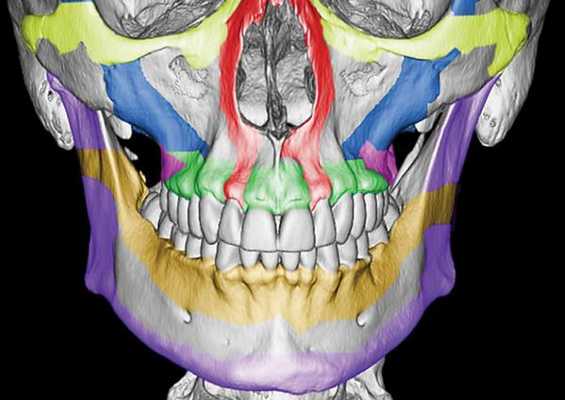

Верхняя челюсть представляет собой достаточно прочную структуру, благодаря местам особой прочности — контрфорсам, которые представляют собой костные утолщения. Различают лобно-носовой, альвеолярно-скуловой, крыловидно-нёбный и нёбный контрфорсы. Забегая вперёд, стоит сказать, что при оперативном лечении переломов верхней челюсти эти "линии" используются для надёжной, ригидной фиксации (остеосинтеза) повреждённых костей.

Классификация и стадии развития перелома верхней челюсти

Чаще всего переломы классифицируют по Рене Ле Фору. Этот французский хирург систематизировал и описал формирующиеся повреждения костей средней зоны лица экспериментально: на головы свежих человеческих трупов он оказывал разные по направлению и силе воздействия по типу тупой травмы. Именно так и было обнаружено, что большинство линий переломов проходит по трём типам [1] :

- | тип — нижний, или горизонтальный тип, перелом Герена — Ле Фора. Перелом проходит над альвеолярным отростком и нёбным отростком через боковую и переднюю поверхности верхней челюсти, от крыловидных отростков основной кости к краю грушевидного отверстия.

- || тип — средний, или пирамидальный перелом, суборбитальный перелом. Линия перелома проходит через корень носа, внутреннюю стенку глазницы и далее — через нижнеглазничную щель кпереди по нижней стенке глазницы к месту альвеолярно-скулового контрфорса с переломом крыловидных отростков. Проще говоря, верхняя челюсть единым блоком "отсоединяется" от остальных костей средней зоны лица.

- ||| тип — верхний тип (поперечный, суббазальный, он же черепно-лицевое разъединение). Самый грозный вид перелома верхней челюсти, когда происходит отрыв верхней челюсти вместе со скуловыми костями от мозгового черепа. Как правило сочетается с тяжёлыми повреждениями головного мозга [3] .

Отличительные признаки каждого типа проявляются по уровню подвижности фрагментов, тяжести состояния больного и данным дополнительных методов исследования (компьютерной томографии).

Помимо классификации Ле Фора существует классификация переломов по Вассмунду, которая отличается лишь отсутствием в линии перелома костей носа. Различают также изолированные переломы отростков, поверхностей и частей верхней челюсти. Однако каждый челюстно-лицевой хирург, занимающийся травматологией, знает, что в жизни всё происходит не совсем так, как написано в книгах. Очень часто верхняя челюсть ломается по другим схемам. Поэтому, готовясь оперировать пациента, хирурги сталкиваются с очень трудоёмкой задачей — им необходимо понять, как собрать этот многооскольчатый "конструктор" с максимальным восстановлением анатомии и функции челюсти через минимальные разрезы с минимальным нарушением кровоснабжения и максимальной стабильностью.